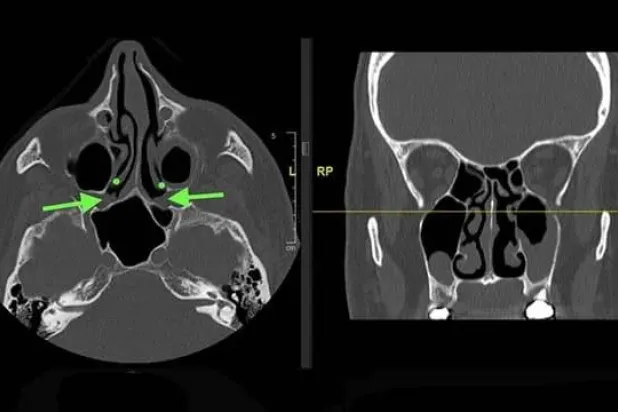

إذا كنت تسمع رنيناً مستمرّاً أو أصواتاً غريبة في أذنك دون مصدر خارجي، فأنت تُعاني مما يُعرف ﺑ«طنين الأذن».